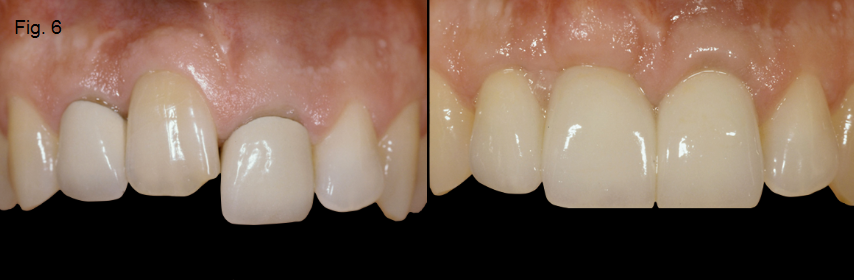

If the ankylosed tooth is an esthetic issue and the rate of the resorption is advancing quickly, extraction of the tooth is recommended. The area will typically require augmentation with either hard or soft tissue, depending if the final restoration is a single-tooth implant or a tooth-supported FPD (Figures 5 and 6).